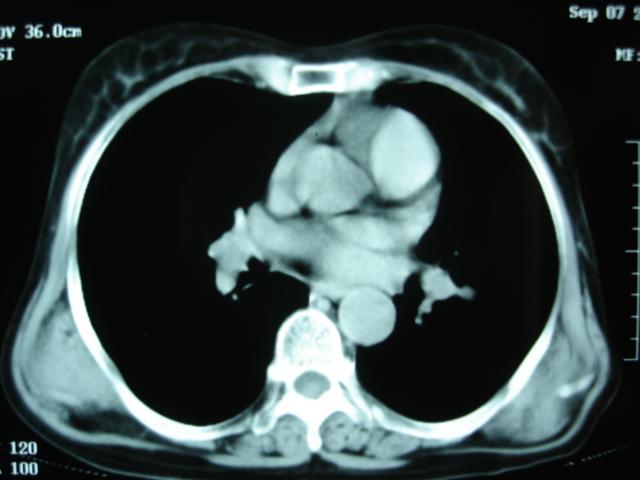

以下是引用卜一在2009-9-7 19:51:00的发言:[br][br] 1 左侧胸内甲状腺占位-多考虑甲状腺腺瘤! 2、左肺门占位-建议增强扫描以便明确性质。 3 慢支并感染! [br]

以下是引用shibing在2009-9-7 20:40:00的发言:[br]左侧胸内甲状腺占位-多考虑甲状腺腺瘤! 2、左肺门占位-建议增强扫描以便明确性质。 3 慢支并感染! [br]